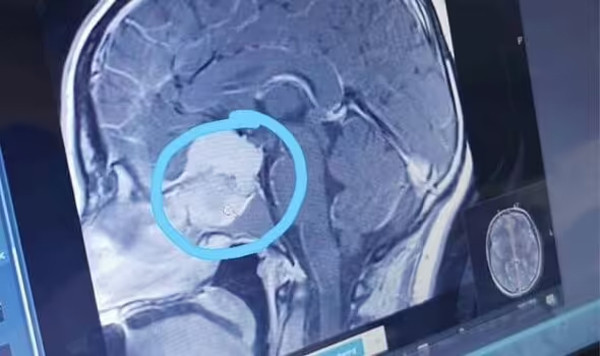

Theo Express, kết quả chụp chiếu của Katie cho thấy một khối u lớn trong não của cô vào tháng 2/2021. Kể từ đó, cô đã trải qua hai cuộc phẫu thuật và quá trình bảo tồn khả năng sinh sản trước khi bắt đầu xạ trị vào tháng 12/2022.